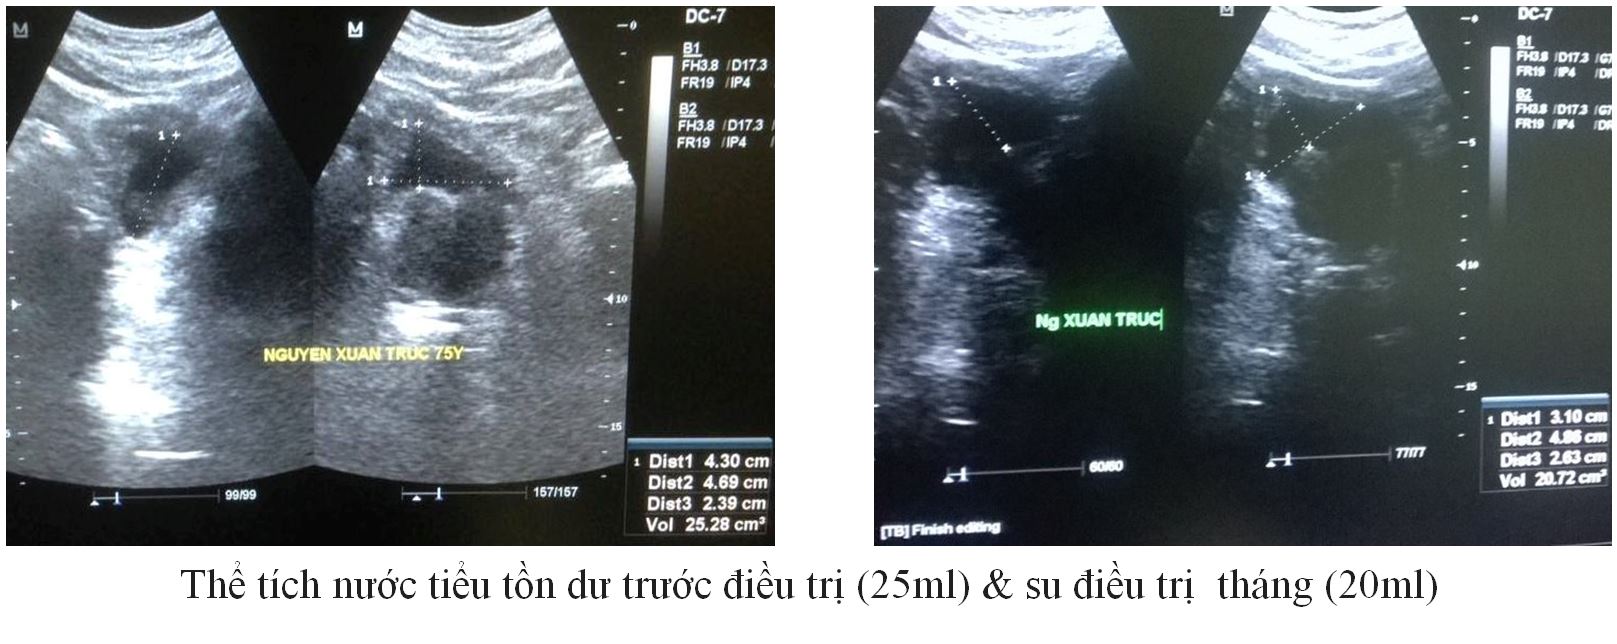

Trường hợp 4:

– BN: Tr, 75 Tuổi / Tiểu đường nhiều năm không mổ

– Tiểu khó, nhiều lần ( 4 lần trong đêm)

– Thể tích TLT 77 gam.

|

Trước ĐT |

Sau 1 tháng ĐT |

IPSS (Điểm) |

16 |

9 |

QoL (Điểm) |

3 |

2 |

PVR (ml) |

25 |

20 |

PV (gam) |

77 |

66 |

PSA (ng/ml) |

1,6 |

– |